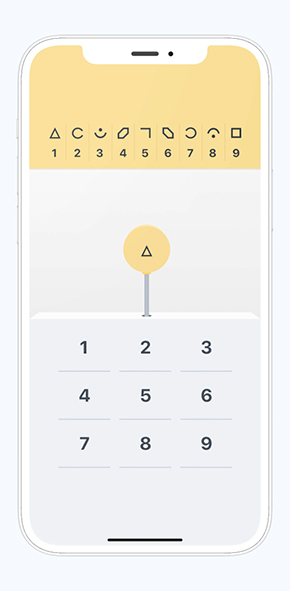

Konectom is leveraging data collected by the sensors available in the smartphone and compatible wearables to allow for quantitative and unbiaised analysis of neurological functions

Inspired by existing assessements recognized scientifically and used in clinical trials

Konectom is leveraging data collected by the sensors available in the smartphone and compatible wearables to allow for quantitative and unbiaised analysis of neurological functions

Inspired by existing assessements recognized scientifically and used in clinical trials